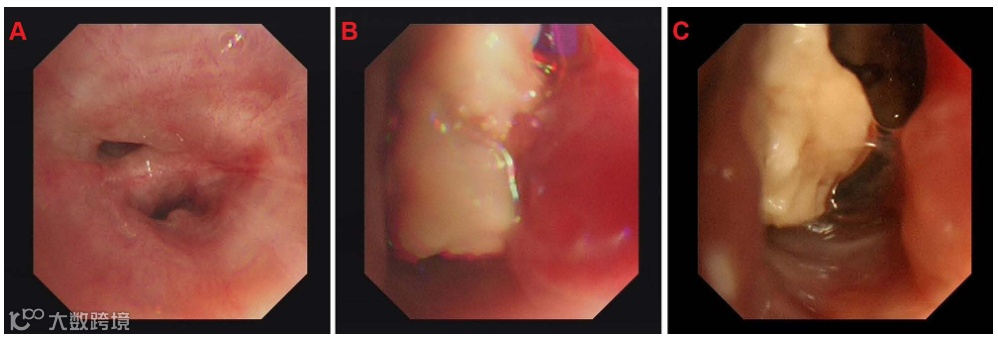

电子支气管镜检查显示左肺下段有一个大的白色肿瘤,开口狭窄,亚段有大量白色坏死物质(图2)。

图2. (A)左下叶开口狭窄。(B和C)左肺下段有一个大而白的肿瘤,亚段有大量白色坏死物。